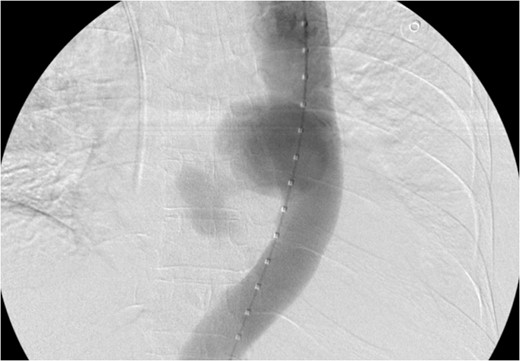

CT scan chest/abdomen/pelvis coronal view. Thoracic pseudoaneurysm distal to the left subclavian artery take off and proximal to the origin of the celiac artery.

Pseudoaneruysm size, anatomical location (distal to aortic arch and above the celiac artery) made it feasible for TEVAR. In the operating room a right groin dissection was performed, stent graft was deployed through right femoral artery and postoperative fluoroscopy imaging showed exclusion of the sac with excellent contained flow within aortic lumen.